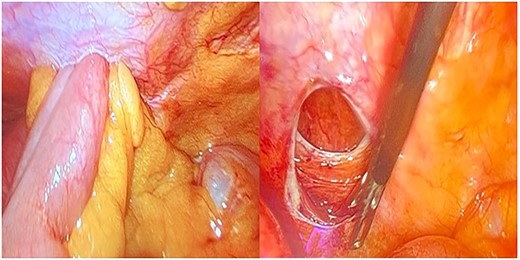

Because of extreme pain and symptom of ileus, a laparoscopic exploration was performed. Laparoscopy confirmed the small bowel herniation in the fascia defect (Fig. 2). The small bowel was captured with an intestinal grasper and repositioning in the abdominal cavity. Then the dehiscence of the fascia was closed with individual absorbable sutures and with semi-absorbable round mesh 6.4 cm in diameter (Ventralex Bard). The small bowel was no ischemic and immediately we recognize peristalsis. The patient after surgery was revealed of her symptoms and she was mobilized the same day. She remained stable throughout her hospitalization and the third postoperative day was discharged. The follow-up lasted for 30 days in our outpatient department.